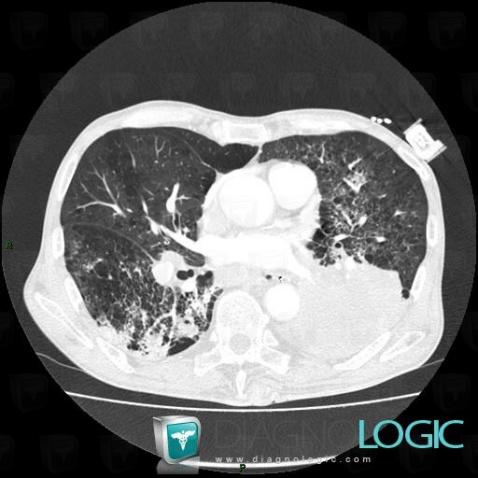

The images below illustrate this case for diagnoses Centrilobular emphysema (link to Emphysema), Bronchogenic carcinoma (link to Obstructive pneumonia), Metastasis, Bronchogenic carcinoma, for the modalities (CT)

Bronchogenic carcinoma, Pulmonary parenchyma, CT

Here is the specific information in the key image above:

- Diagnosis Bronchogenic carcinoma (link to Obstructive pneumonia), Location(s) Pulmonary parenchyma, with gamuts Localized consolidation, Chronic consolidation

- Diagnosis Bronchogenic carcinoma, Location(s) Pulmonary parenchyma, with gamuts Pulmonary mass with hilar attachment, Solitary pulmonary mass